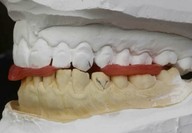

Mascherina in silicone trasparente e di compositi iniettabili: i protagonisti della Injectable technique

► Mock-up e pre-visualizzazione

► Creazione di un indice in silicone trasparente

Galleria fotografica